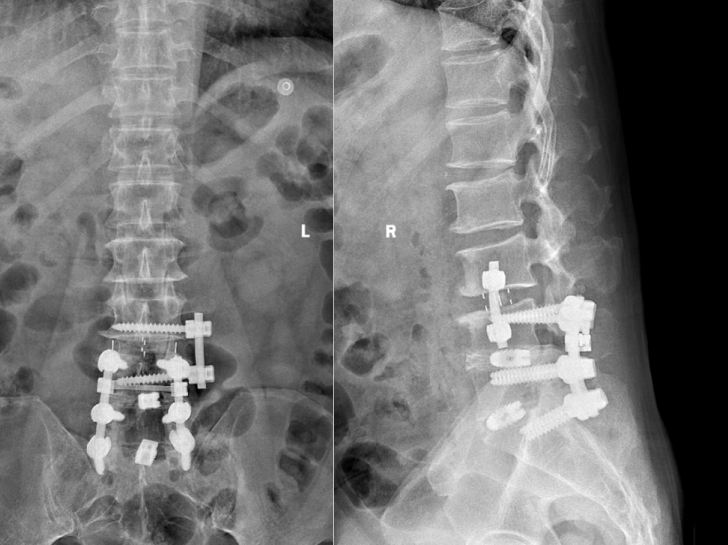

术后复查x光片提示腰椎内固定位置良好